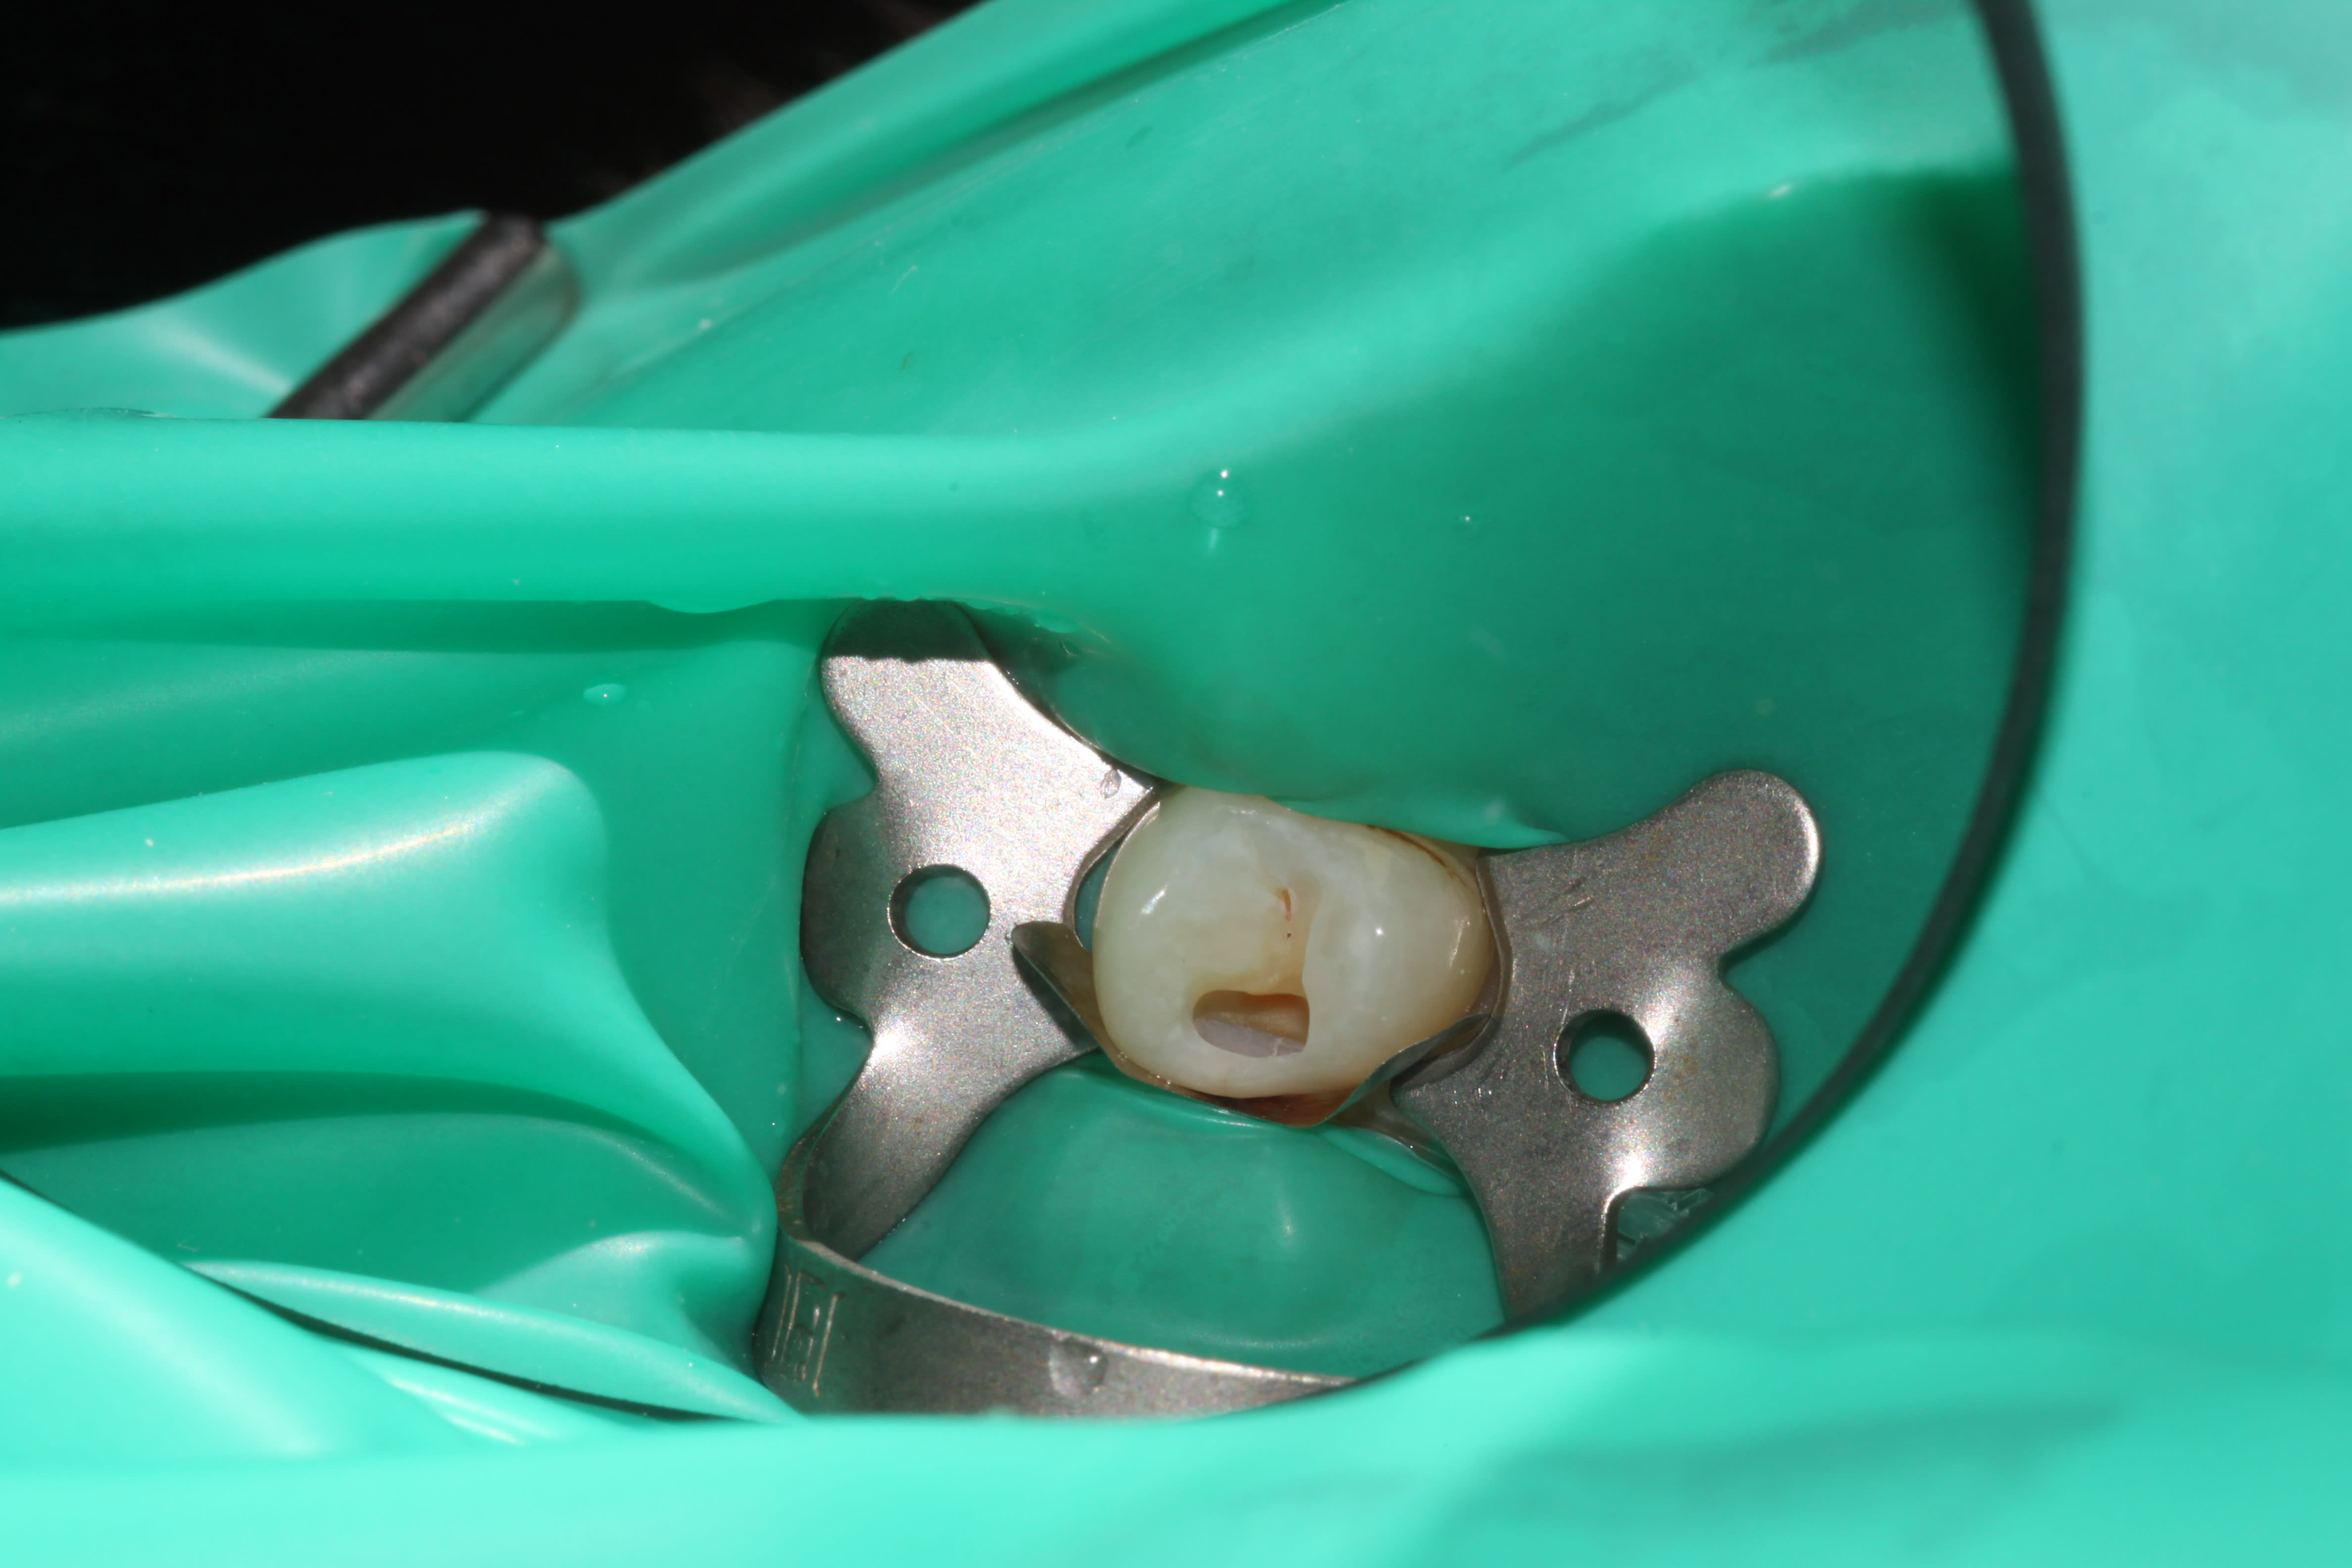

retour apres qq mois egalement

je ne fais que des cavité tunnelisé pour eviter de casser la crete marginal qui est tres galere a recontruire rapidement

Difficulté: j'ai parfois quelques bulles (1 fois sur 10) dans la masse du compo (je laisse comme telle quand c'est le cas) malgré le fait de faire attention a chaque fois, des astuces pour etre sur a 100% de ne pas avoir de bulles ?

obligé de faire une preparation dans le sillon occlusal pour pouvoir anguler la fraise au maximum et bien nettoyer la carie.

Aucun pb post op pour le moment, pas de crete qui s'est fracturé, pas d'endo, pas de sensibilité post op

Puisque le sujet a été évoqué récemment, je relance, du matin.

J'en avais une autre prévue mais la crête a pété lors de l'éviction carieuse, pas grave mais du coup je ne pouvais pas présenter de photos.

Preuve donc que ce n'est pas si compliqué.